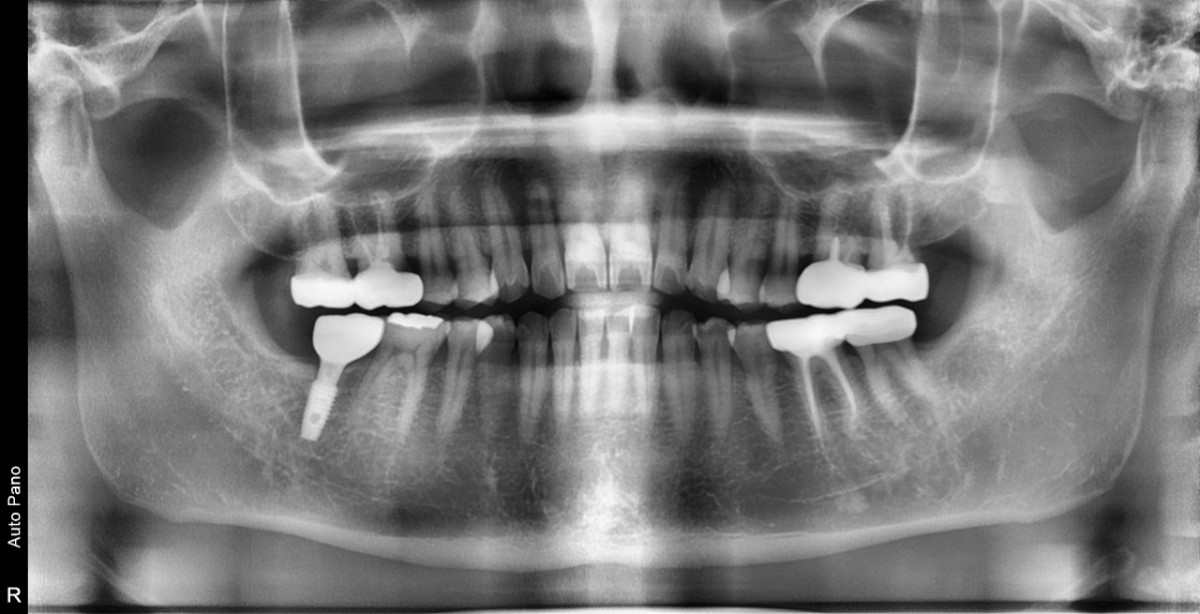

Single implant (staged) Arum NB1, f/u

A 47-year-old male patient had a crown with an ill-fitting margin and crack-tooth syndrome in the lower 2nd molar. No systemic issue.